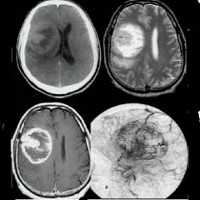

Наилучшими способами объективного выявления опухоли полушарий мозга признаны методы нейровизуализации: КТ и МРТ головного мозга. Они позволяют определить точную локализацию опухоли полушарий мозга и дифференцировать ее от внутримозговой гематомы, кисты при сирингомиелии, абсцесса головного мозга, рассеянного склероза, эпилепсии. Однако поставить достоверный диагноз и верифицировать опухоли полушарий мозга позволяет лишь гистологическое исследование. Оно может проводится с образцами мозговой ткани, полученными в ходе стереотаксической биопсии или интраоперационно.

Подозрение на объемное образование головного мозга является однозначным показанием к проведению компьютерной или магнитно-резонансной томографии. КТ головного мозга позволяет визуализировать опухолевое образование, дифференцировать его от локального отека церебральных тканей, установить его размер, выявить кистозную часть опухоли (при наличии таковой), кальцификаты, зону некроза, кровоизлияние в метастаз или окружающие опухоль ткани, наличие масс-эффекта. МРТ головного мозга дополняет КТ, позволяет более точно определить распространение опухолевого процесса, оценить вовлеченность в него пограничных тканей. МРТ более результативна в диагностике не накапливающих контраст новообразований (например, некоторых глиом головного мозга), но уступает КТ при необходимости визуализировать костно-деструктивные изменения и кальцификаты, разграничить опухоль от области перифокального отека.